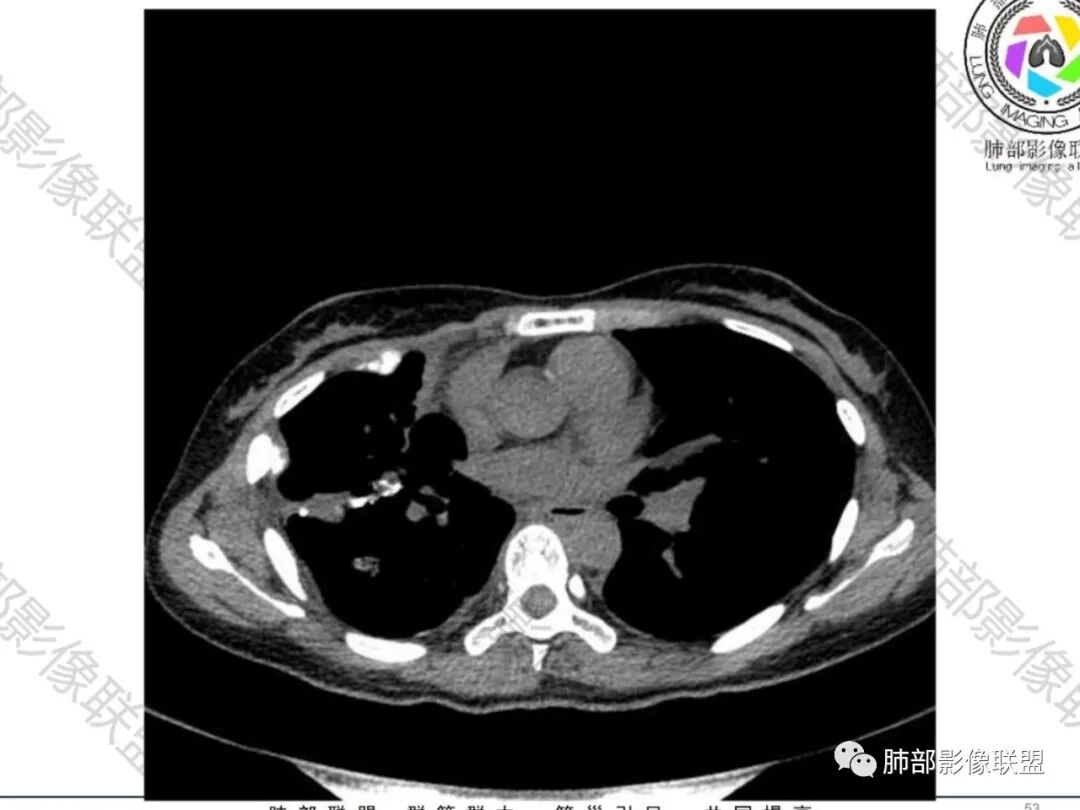

傅昌瑜:青年女性,咳嗽胸痛2月,偶有血痰。双肺上叶多发不规则肿块,密度不均匀,内部可见点状、条片状钙化影,右上肺病灶空洞,壁厚薄不均,见壁结节,与支气管关系不清,两侧胸膜增厚,见多发结节,部分结节边缘膨隆明显,结节内亦有多发钙化。上述改变常见于结核、尘肺、钙化性转移等疾病。有膨隆感的结节考虑转移可能性大。

尘缘:青年女性,痰中带血,胸痛2月,无发热盗汗,实验室检查,有贫血,总蛋白降低,血沉情况未知,肿标基本正常。影像表现:双上肺小叶间隔增厚,双侧胸膜广泛不规则增厚,胸膜下多发肿块伴不规则钙化,右侧肋骨破坏。纵隔淋巴结肿大不明显,双肺门淋巴结肿大,部分融合,分析思路:一、感染性病变,1、结核,青年女性,胸膜增厚,多发肿块伴钙化,有咳嗽胸痛,痰中带血,要考虑,但无结核中毒症状,病史仅两月却钙化太明显,肺内没有明显树芽征,存疑,2、其他感染,无炎性指标支持,白细胞不高,可能性小。二、非感染性病变,1、尘肺,胸膜增厚,钙化,胸膜下钙化性肿块,要考虑,但肺内无粉尘结节,无职业史,可能小。2、转移性钙化,无肾脏病史,无血清钙磷代谢异常指标支持,肺内间质无钙沉积改变,基本排除。三、肿瘤性病变,1、肺癌伴转移,双上肺有小叶间隔增厚,双肺门有淋巴结肿大,要考虑,但青年女性,病史两月,钙化太多太广泛,肿标基本正常,可能性小。2、骨肉瘤转移。15-30岁青年人,是骨肉瘤高发年龄,肺内多发成骨样钙化转移灶,双上肺小叶间隔增厚符合癌淋样表现,右侧肋骨破坏,要高度怀疑,需要详细询问病史及手术史。3、软骨来源肿瘤伴肺内转移,右侧肋骨虽有破坏,但无明显软骨样破坏及钙化。可能小。4、其他肿瘤伴转移,青年女性,其他恶性肿瘤能广泛发生钙化性转移的可能性小。综上所述:骨肉瘤伴右侧肋骨及胸膜转移,胸膜下转移,肺内癌淋可能最大,结核不完全除外,下一步需要,仔细询问病史,如果有骨肉瘤史,则基本确诊,如果没有,需要进一步问询呼吸系统症状,病程,以前的影像对照,了解肾脏情况,查血清钙磷指标。

南边:那就是说这个肋骨是自身的病变,有成骨性骨质破坏

从这个角度区看肺部/胸膜的病变,想法就不一样

空洞——恶性特点

胸膜结块,有侵袭性

但是都有多发钙化

肋骨伴随有溶骨性/成骨性骨质破坏,常规还是要警惕恶性